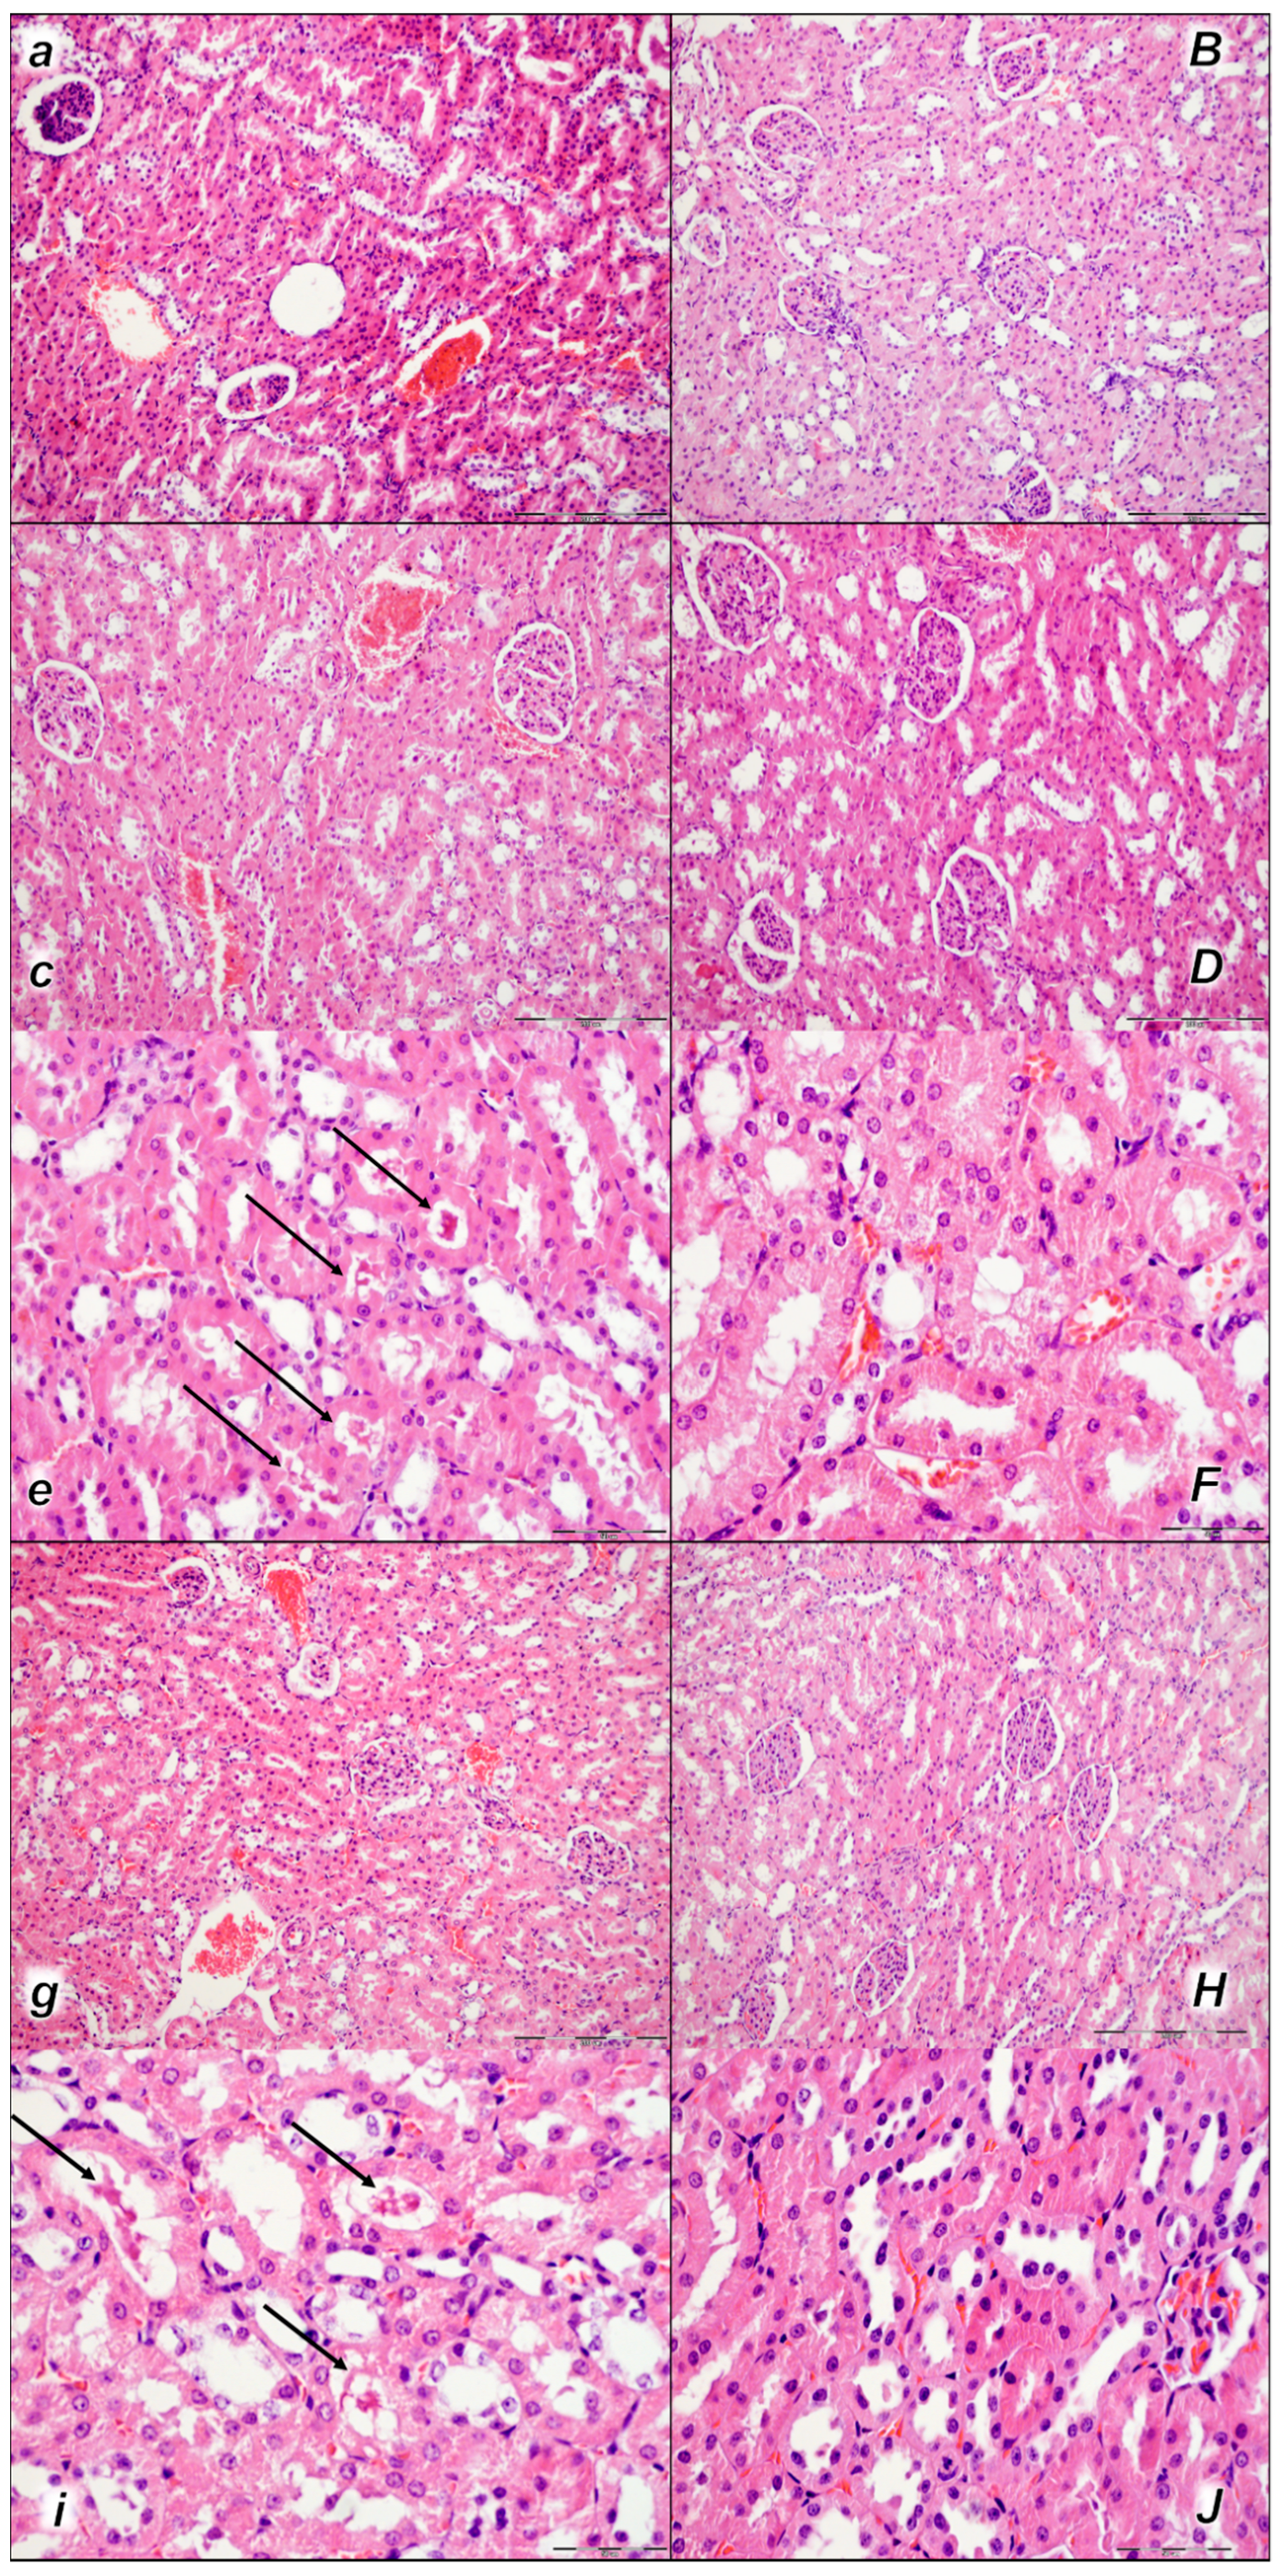

Pronounced dilatation of sinusoids and branches of the portal vein in portal tracts was found in the liver tissue of control rats in all three assessment time periods (15 min, 30 min, and 60 min following application). No changes were found in BPC 157-treated rats in the first two assessment time periods (15 min, and 30 min), and only mild congestion of liver parenchyma was found at 60 min following application (Table 4, Figure 8).

Figure 8.

Liver, microscopy presentation (a–F). In liver parenchyma, pronounced dilatation of sinusoids and branches of the portal vein in portal tracts was found in liver tissue of control rats (small italic letters) at 15 min (a), 30 min (c), and 60 min (e) after laurate application into the inferior caval vein. No changes in BPC 157-treated rats (capital italic letters) were observed at 15 min (B), 30 min (D), and 60 min (F) after laurate application into the inferior caval vein. (HE staining; magnification 400×; scale bar 100 μm).